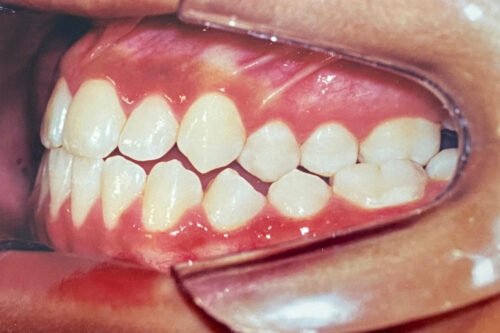

Tratamento em fase de finalização

IMAGENS REAIS – sem qualquer tipo de manipulação!

Em Tratamento